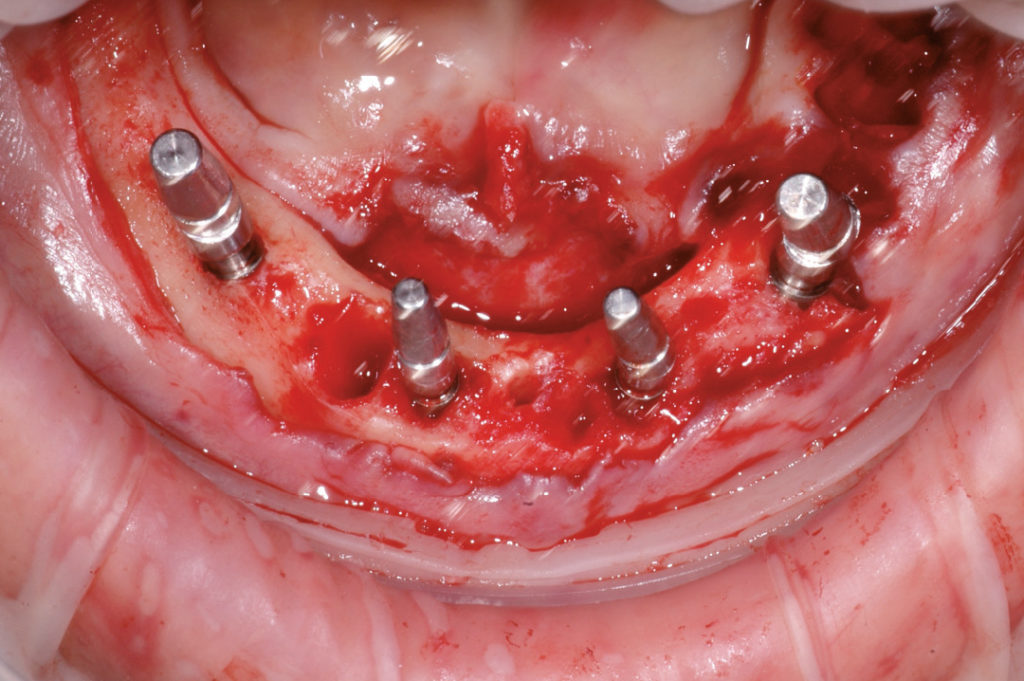

Vista clínica después de la extracción de los dientes restantes, colgajo mucoperióstico de espesor completo, desbridamiento quirúrgico, limpieza y aplanamiento de la cresta residual

Los transferes están atornillados sobre los MUA seleccionados y los pilares están colocados sobre los implantes: dos pilares angulados a 35° GH 3 para los implantes inclinados, un pilar recto y uno angulado a 15° GH 3 mm para los implantes anteriores

Los MUA rotan hasta que se alcanza el paralelismo

Una vez determinadas las posiciones correctas, se quitan los transferes y se activan los pilares en los implantes

Se reposicionan los transferes sobre los MUA, cierre de la herida con suturas reabsorbibles